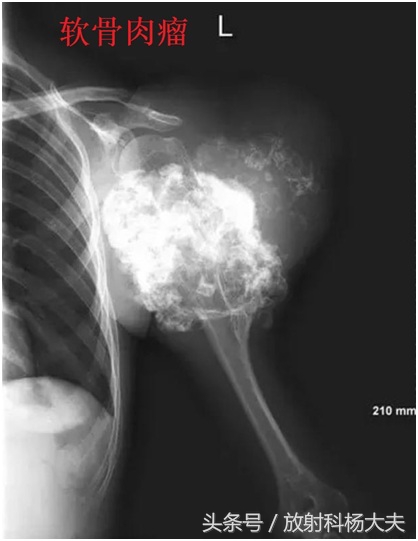

在骨关节的X线片上,通常在骨骼或骨骼边上看到这种高密度的类似骨骼一样东西,我们会考虑哪些?骨肉瘤,软骨肉瘤,创伤性骨炎,还有某些疾病引起的钙化,骨化等等。

比如,下面的图,都是恶性的。